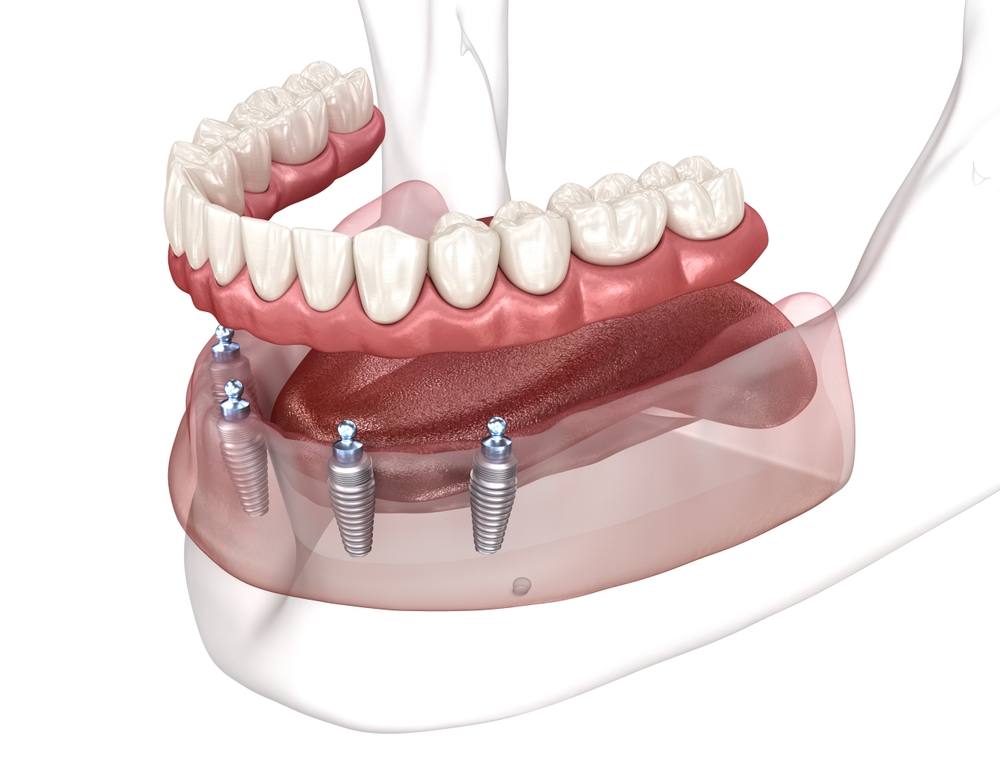

When you lose a tooth, whether from injury, decay, or other dental issues, you don’t have to live with that gap forever. Modern dental implants